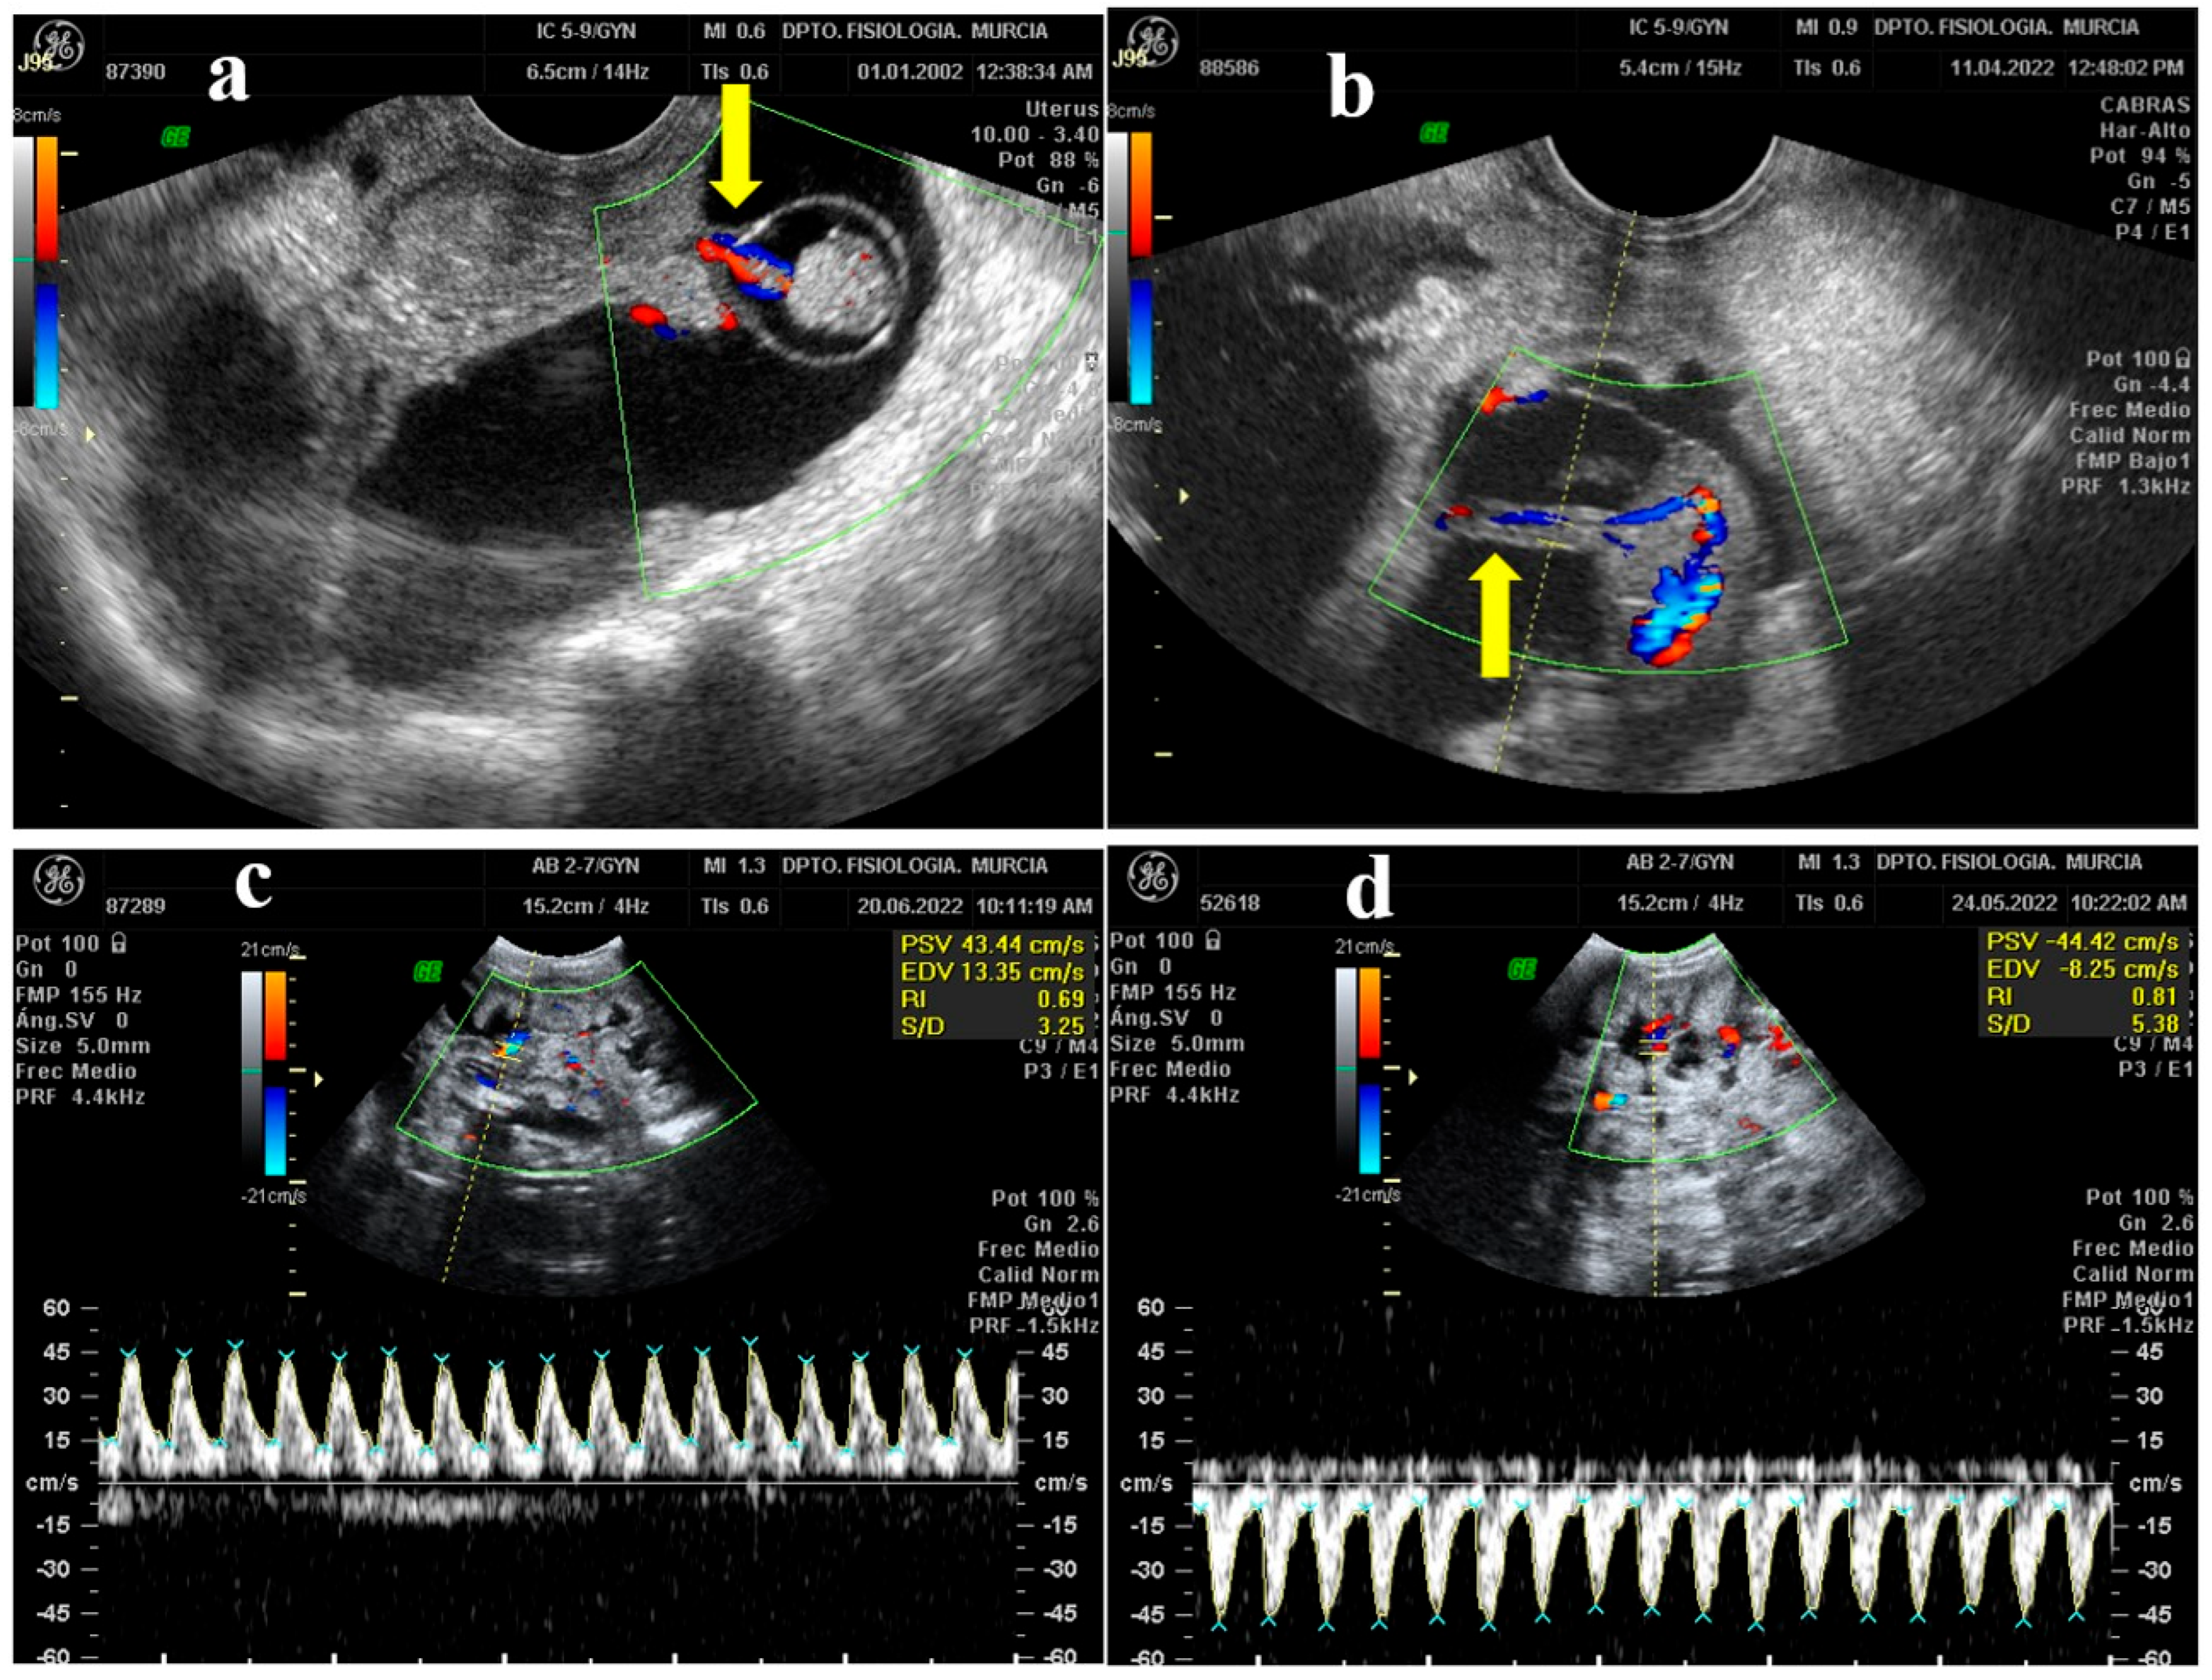

B-mode enables the capacity to study the moment in which the umbilical cord begins to be glimpsed for the first time (Figure 2a). In the first cord sightings, a small structure was observed next to the embryo, so that it could be located with an elongated or rounded shape as the fetus grew (depending on whether the section we observed was longitudinal or transversal) and floated in the amniotic fluid.

Figure 2.

Ultrasound images of the study of the umbilical cord of M-G breed goat fetuses. (a) Early identification of the umbilical cord (arrow) of the embryo (32 dpm). (b) Color Doppler ultrasound identification of the umbilical cord (arrow), where red colors reflect blood approaching the transducer and blue colors reflect blood moving away. (c) Umbilical arterial flow waves by color Doppler and spectral Doppler, where blood flow is directed towards the transducer and shown with positive values above baseline. (d) In this image, the flow is moving away from the transducer and is represented by negative values below the baseline. PSV: Peak Systolic Velocity. EDV: End Diastolic Velocity. RI: Resistance Index. S/D: Systolic/Diastolic Ratio.

Once the umbilical cord was found thanks to the B mode, it was verified that it was this structure using color Doppler and observing the red-blue color pattern that indicates the presence of positive or negative blood flow (Figure 2b). Next, it was analyzed by spectral Doppler. To begin with, the Doppler caliper was placed over the umbilical artery and the examination began. The graph obtained with the spectral Doppler study on an artery showed the waveform systole and diastole for each cardiac cycle with a characteristic sawtooth shape. However, a vein gave a constant graph since it does not present a pulse pattern. Subsequently, while the graph is displayed, the ultrasound machine transforms the ultrasound into the sound of pulsations. In the case of arteries, this sound was rhythmic and pulsating, while the result of the veins was constant and without a defined pulse.

The wave formed by the Doppler when the umbilical artery is analyzed resembles saw teeth, while vein shows a horizontal graph corresponding to the continuous flow of the vein, without pulsations. As is observed from the red and blue pattern of the color Doppler, the vessel measured approaches (red) or moves away (blue) from the transducer. This is translated in the spectral Doppler plot, in which the waves lay above (positive values) or below (negative values) the baseline (Figure 2c,d).